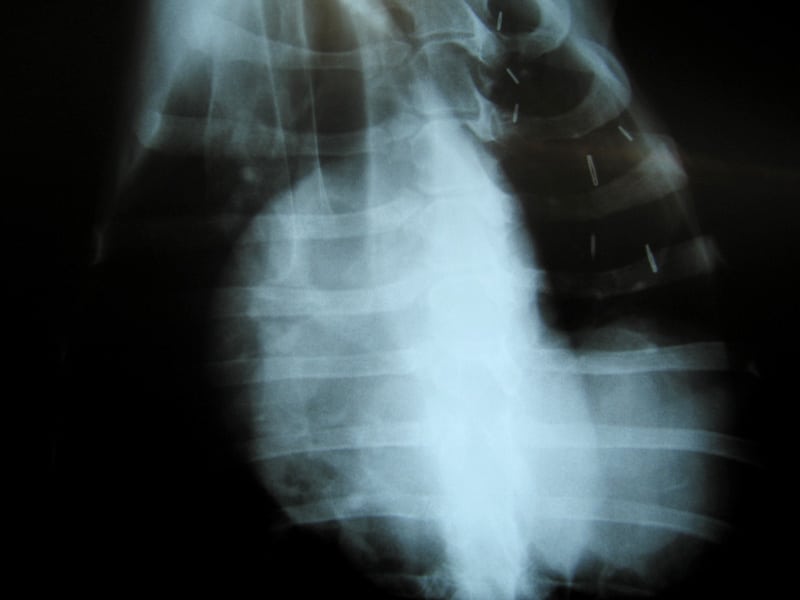

Tomorrow we’ll get the results from tests on blood and urine samples they took from me. But the films clearly indicate that I do indeed have a lump in my lung. More of a mass really, about the size of a softball from the looks of things. But as I have proven all along, I’m a special case.

osteosarcoma metastasis xrayUsually, osteosarcoma metastasis presents itself as multiple legions throughout the lungs. The doctor expected to see a “snowstorm” on the x-rays. And I could tell my people did too, deep down inside. Instead, I appear to have a single large growth, which may or may not be operable.

In fact, it may or may not have anything to do with my cancer at all. That’s probably not the case, but the doctor did mention the rare possibility that it could be totally unrelated. Perhaps he was just trying to keep our hopes up.